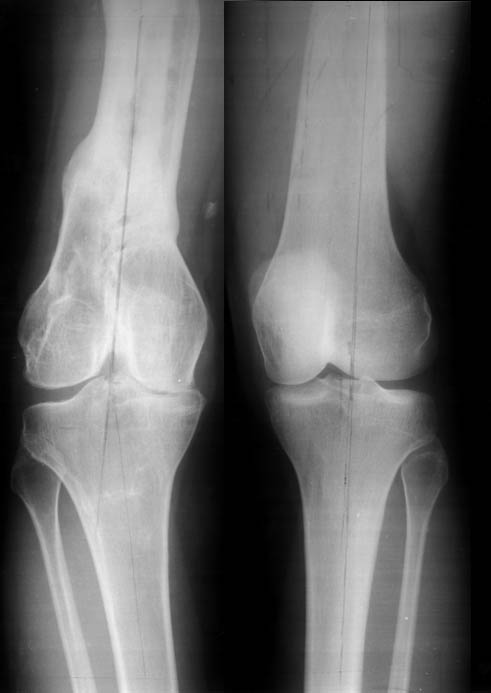

Женщина, 29 лет.В 2001 году получила политравму (таз, открытый многооскольчатый перелом правой бедренной кости на границе средней и нижней трети со смещением,

открытый перелом правой голени, пятки, закрытый - правого надколенника, поперечного отростка L4, пальцев кисти, сотрясение головного мозга).

Переломы конечностей лечились АВФ.В настоящее время стойкая разгибательная контрактура правого коленного сустава (сгибание 105-110 гр., разгибание 160-165 гр.), варусная деформация, болевой синдром.

Даже по этим коротким снимкам видно, что варусная деформация на уровне бедра. Хотя для полноценной оценки оси сделать надо снимок всей конечности, от таза до стопы. Наклеить метки на кожу, по которым сделать склейку. И профиль бы тоже неплохо посмотреть.

Уважаемый Антон, видимо перелом большеберцовой кости на механическую ось не повлиял, но явно варусная деформация усугубляется повреждением наружного связочного аппарата (МКС.... Просится поднагрузочный R-снимок конечности и корригировать, на мой взгляд, надо бедро (+ остеотомия, если планируется мобилизация коленного сустава).